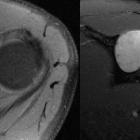

Peripheral

schwannoma mimicking a bone tumour. The lesion shows intense and homogenous enhancement after the administration of Gadolinium. Note the preserved rim of very thin cortical rest (arrow).